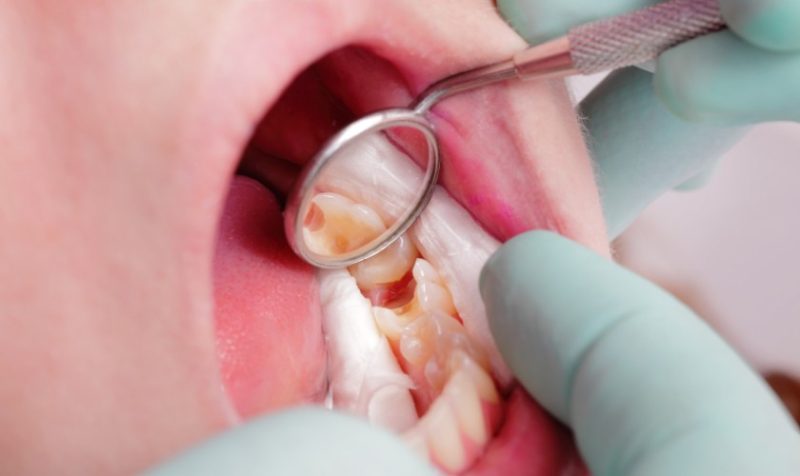

Điều trị bằng phương pháp nha khoa

Sử dụng các phương pháp nha khoa trong điều trị viêm tủy có mủ không chỉ mang lại hiệu quả lớn mà còn đảm bảo an toàn, với mọi quy trình đều được thực hiện trong điều kiện vô trùng, giảm tối đa nguy cơ viêm sưng và nhiễm trùng.

Sau khi hoàn thành quá trình kiểm tra và xét nghiệm ban đầu, hầu hết các bác sĩ sẽ đề xuất một kế hoạch điều trị cụ thể cho từng bệnh nhân. Họ sẽ thực hiện gây tê tại vị trí của tủy răng bị viêm, sau đó rửa sạch tất cả các ống tủy và buồng tủy bị nhiễm trùng để chuẩn bị cho quá trình hàn trám và bít lại phần tủy đã bị tổn thương.